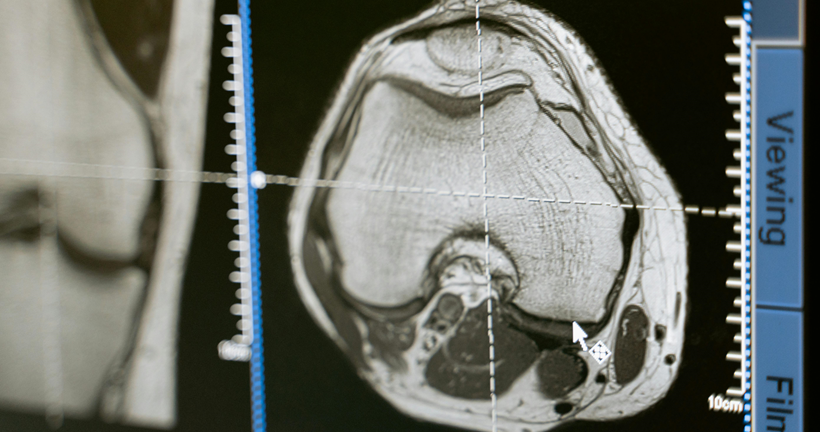

La presentación sintomatológica de la disfunción frontal dependerá de si la afectación predominante inmiscuye a regiones del cíngulo u orbitales. Además, las afectaciones de las funciones ejecutivas dependerán del daño en la corteza dorsolateral. Buscamos describir la relación existente entre la atrofia cerebral identificada en estudios de resonancia magnética estructural, PET-FDG y su implicación cognitiva sobre los pacientes con DFTvnf.

Como resultados en relación con los estudios analizados, se encontró que solo el 15% de artículos mantienen una correlación de áreas anatómicas - cognitivas, además se encontraron alteraciones en los dominios de atención, memoria y funciones ejecutivas mientras que los hallazgos de atrofia cerebral se localizan en áreas frontales, el cíngulo e ínsula.

El diagnóstico de la DFTvnf es un proceso complejo que se compone de distintas etapas, por lo que, la presente revisión sistemática confirma la importancia de estudio de las manifestaciones clínicas, la evaluación neuropsicológica de procesos cognitivos y el papel de las técnicas de neuroimagen en la identificación de este tipo de variantes.